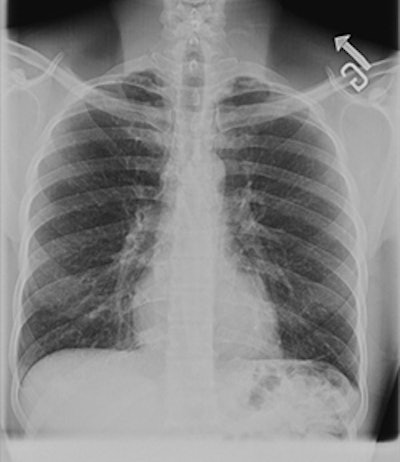

![]() |

| GE is featuring its PET/CT MotionFree imaging technology in its RSNA booth. |

Through motion-free imaging, the technology could enable physicians to see disease earlier, localize and personalize treatment, and carefully monitor treatment.

GE's new version of the Discovery Dimension PET/CT scanner will include motion-free imaging. The system's features include motion-correction techniques to enhance clinical results and minimize blur caused by motion. For patients, the result can be enhanced radiation treatment planning through more accurate tumor delineation for a more precise treatment plan.

GE's Vue Point HD PET image processing application also is designed to improve small lesion detectability. Available on Discovery Dimension with new installations or by field upgrades for installed Discovery ST systems, the upgrade enables clinicians to perform advanced PET image generation for both qualitative and quantitative accuracy.

Vue Point HD incorporates proprietary advanced image reconstruction algorithms, including volume scatter correction and a patented image projection technique. It is applicable to both 2D and 3D PET acquisition modes, as well as static, dynamic, and motion imaging.